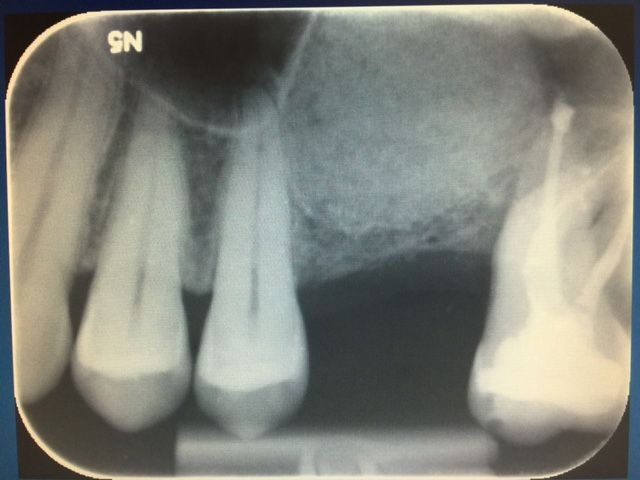

CAS N°2